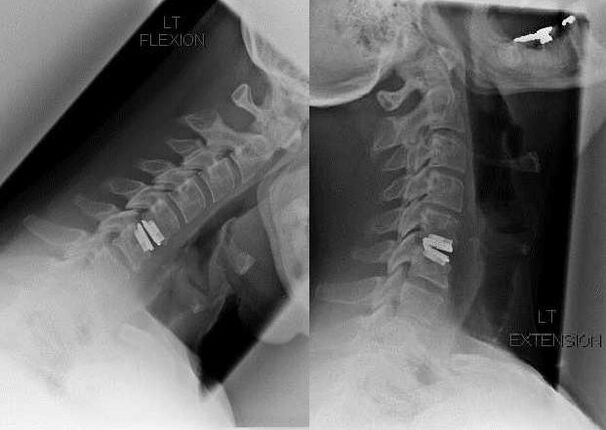

L'osteocondrosi cervicale è trattata con metodi conservativi e il trattamento è sempre completo. La terapia farmacologica è la stessa per l'osteocondrosi di qualsiasi dipartimento: utilizzare farmaci di determinati gruppi farmacologici, ma la scelta di farmaci specifici di questi gruppi, il dosaggio, la durata dell'assunzione è selezionata individualmente per ciascun paziente. L'immagine a raggi X della colonna cervicale dopo il trattamento chirurgico delle vertebre C5 - C7 è integrata da un indice temporaneo di un colletto Chanstz o delle sue varietà. A causa della fissazione delle vertebre cervicali, l'osteocondosi della regione cervicale viene trattata più velocemente. Questo ulteriore dispositivo ortopedico aiuta a far fronte al dolore, normalizza il flusso sanguigno attraverso i vasi del collo e migliora le condizioni generali del paziente.